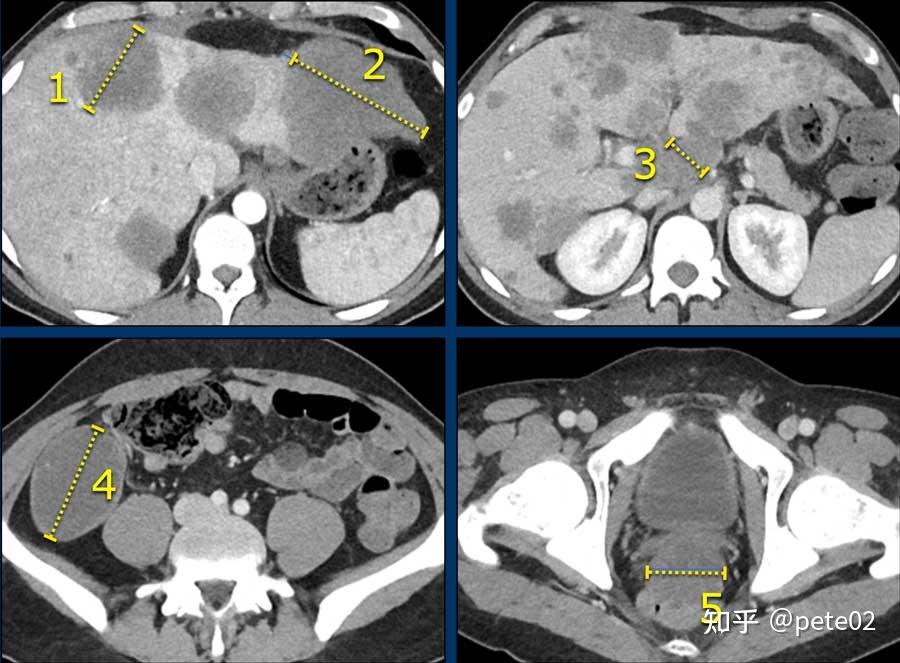

实体肿瘤疗效评价标准:recist 1.1 - 知乎

图片尺寸900x663